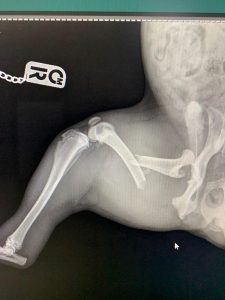

- Hirurške intervencije na zglobovima(artrotomija, artrodeza)

- Liječenje rupture prednjeg križnog ligamenta koljena TPLO (eng. Tibial Plateau Leveling Osteotomy)